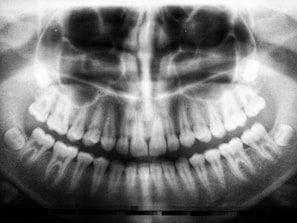

Surgical wisdom tooth removal

Our expertise in surgical procedures allows us to safely and efficiently remove wisdom teeth and other impacted teeth, resolving your current discomfort and preventing future complications.

Surgical management of jaw cysts and tumours

With a focus on precision and patient safety, we provide expert surgical removal of jaw cysts and tumors. Our thorough approach ensures a comprehensive treatment plan and meticulous care for a full recovery.